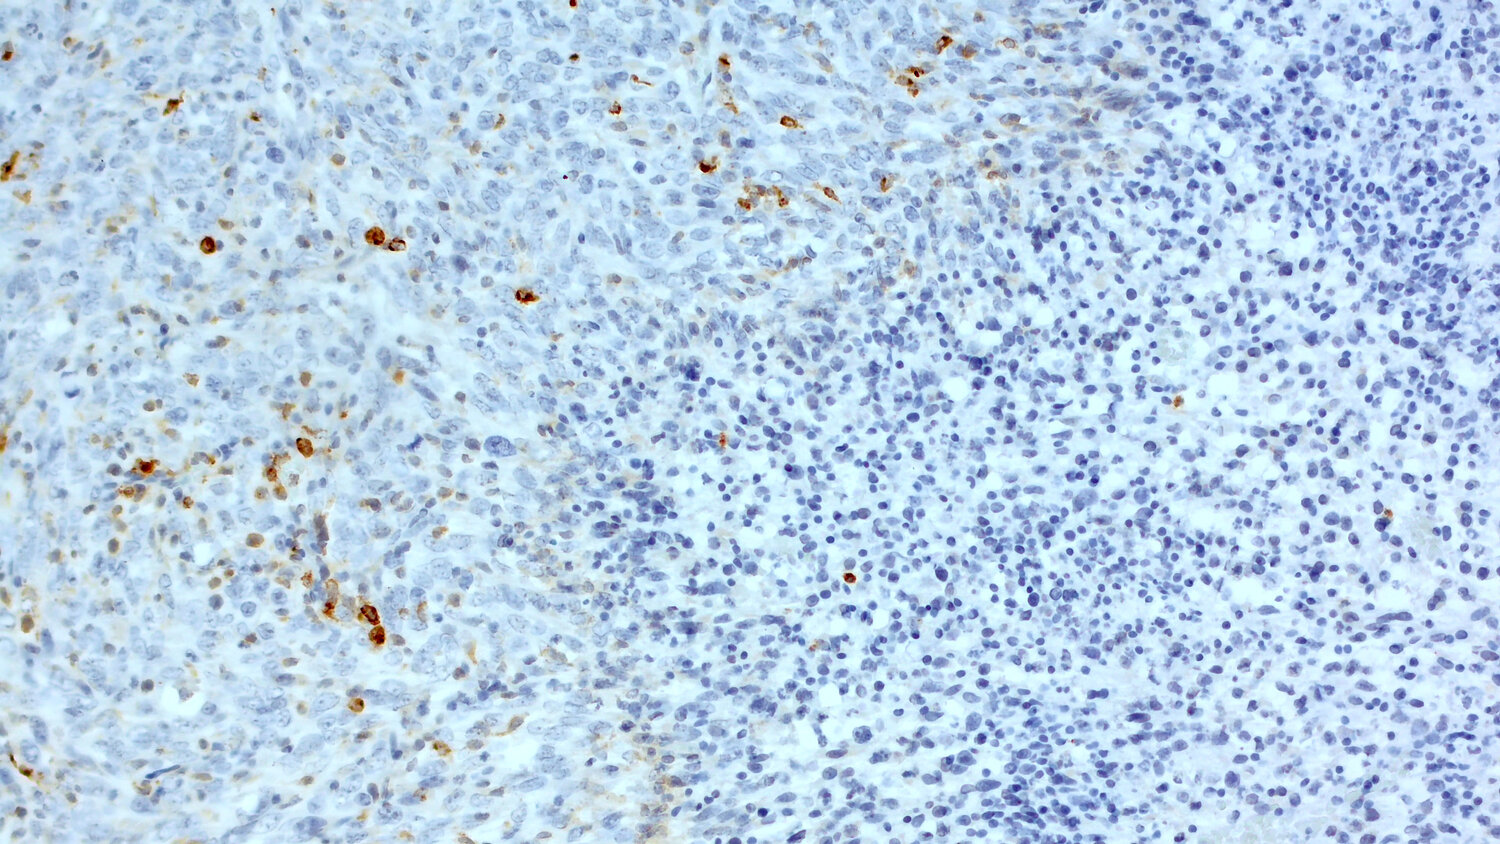

Antigen-presenting cells are important for the induction of anti-tumor immunity by priming naïve T-cells to differentiate into effector cells. As CD11c is highly expressed in human monocyte derived and in human conventional DCs, CD11c+ cells can be found in human tumors to be located in areas with high numbers of tumor-infiltrating lymphocytes (TILs). Therefore, high CD11c expression is associated with a longer median overall survival in patients e.g., with gastric cancer (Wang et al., 2015) or high-grade serous ovarian cancer (Corvigno et al., 2020). Furthermore, experiments in syngeneic mouse models in immunocompetent mice show that CD11c+ dendritic cells play a critical role in the tumoricidal activity of antibody therapies (Haynes et al., 2010). Therefore, histological detection of CD11c+ cells in syngeneic mouse models is an essential biomarker in pre-clinical oncology (figure 6).

Immunohistochemical staining for CD11c in formalin-fixed paraffin embedded sections of a murine breast cancer

Figure 6: Immunohistochemical staining for CD11c in formalin fixed paraffin embedded (FFPE) sections of a murine breast cancer (EMT6; kindly provided by Charles River, Freiburg, Germany) using A rabbit anti-CD11c (HS-375 003, 1:100, DAB) or B guinea pig anti-CD11c (HS-375 004, 1:1000, DAB). Nuclei were counterstained with hematoxylin (blue).